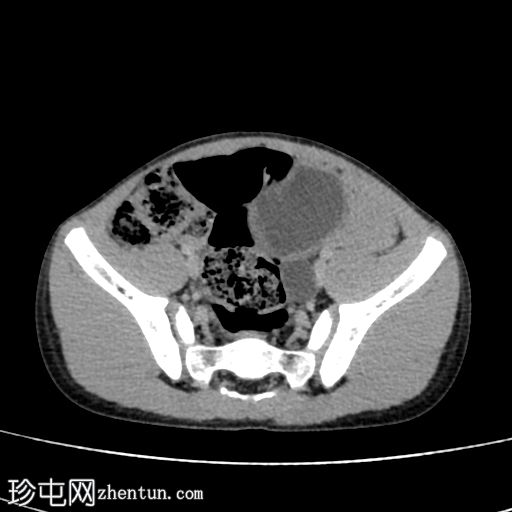

轴位肾盂期

3.jpg

排泄期

4.png

在这张多期增强CT图像中,我们可以观察到肾盏、肾盂以及左侧输尿管全程扩张。

未见感染或其他相关征象。